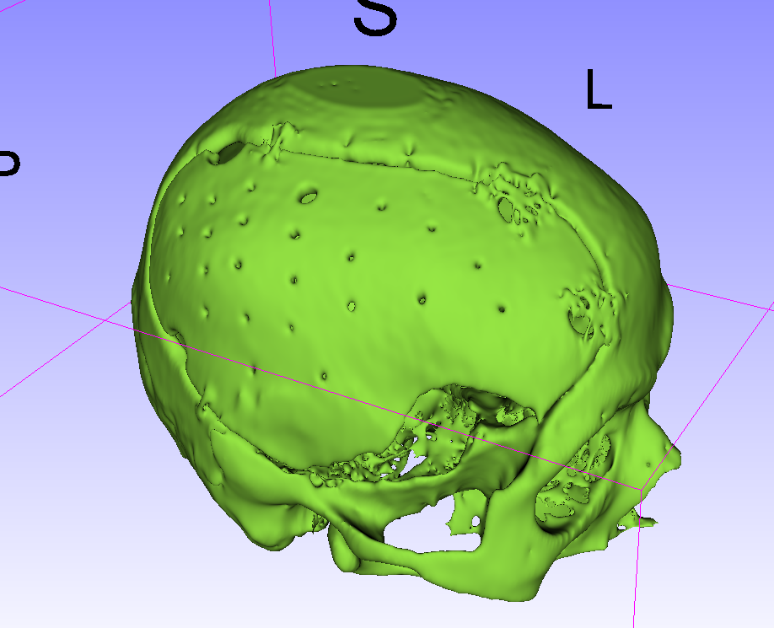

病例1:自体颅骨修补术前,去骨瓣术后2个月CT:

自体颅骨修补术术后CT:

病例2:自体颅骨修补术前,去骨瓣术后3个月CT: